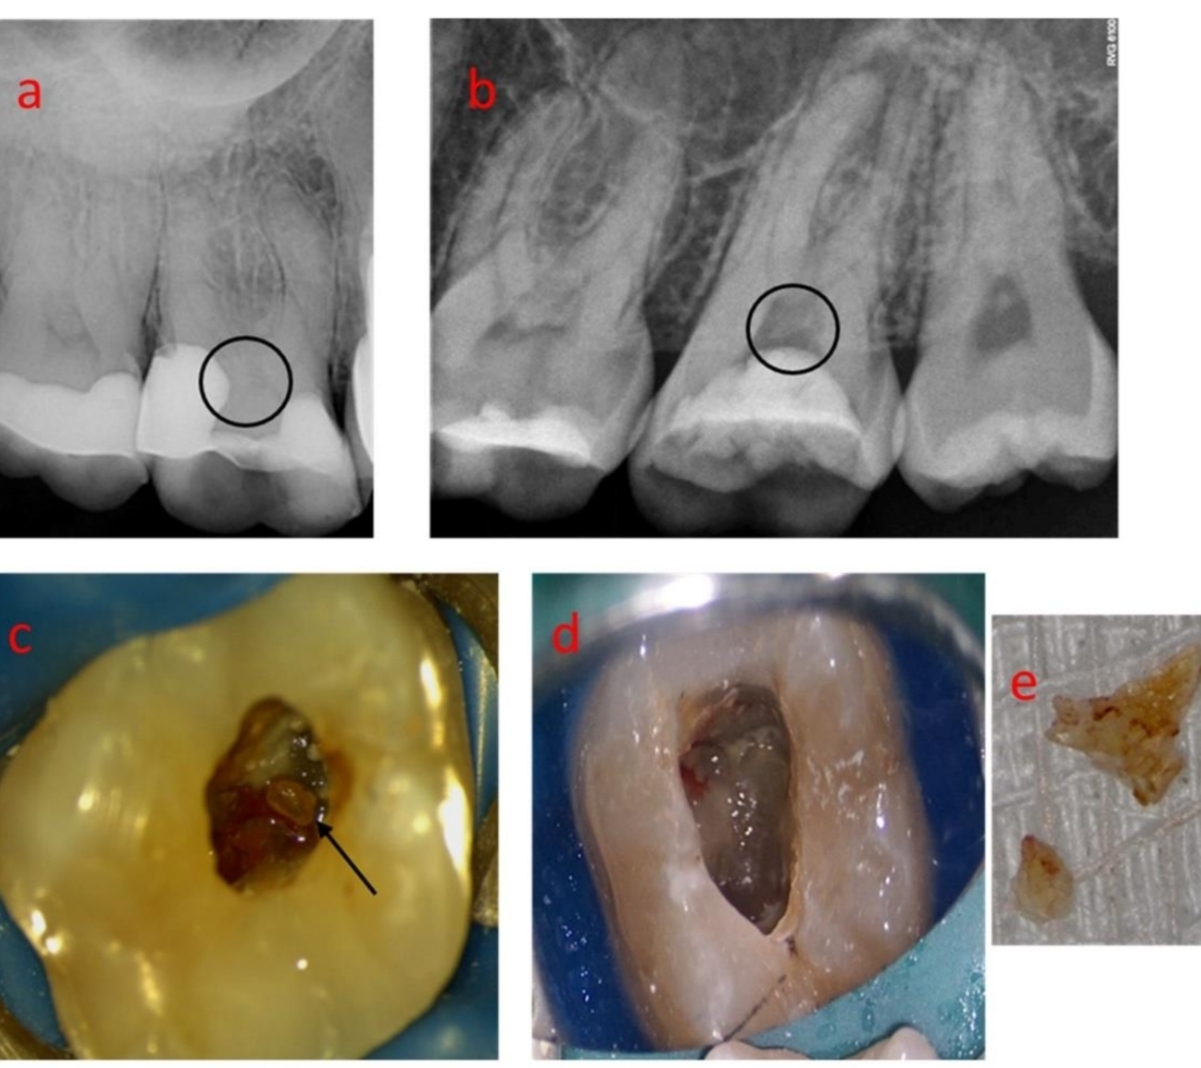

What is calcific metamorphosis and what appearance can it give the crown?

Tooth’s trauma response - canal partially/completely filled with hard tissue

Yellow discoloration of crown